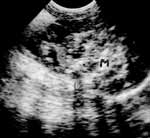

За время пребывания в отделении детей раннего возраста 3-ей детской клинической больницы не было выявлено соматической и инфекционной патологии, изменений со стороны клинико-лабораторных показателей. Опухоль выявлена случайно при проведении ультразвукового исследования органов брюшной полости. Визуализировалось объемное тканевое образование с неровными нечеткими контурами, неоднородной внутренней эхоструктуры размером 40х50 мм, сливающееся с верхним полюсом правой почки (Рисунок). У верхнего полюса левой почки, оттесняя селезенку, визуализировалось объемное образование несколько меньших размеров с неоднородной эхоструктурой, сниженной эхогенности. Данное образование отличимо от опухоли Вильмса экстраренальным расположением, неоднородной эхогенностью. Гемодинамика брюшного отдела аорты и её висцеральных ветвей не нарушена. Заключение: объемное образование обеих почек. В последующем ребенок переведен в детский онкогематологический центр.

Рисунок. Нейробластома. В проекции правого надпочечника визуализируется тканевое образование с неровными нечеткими контурами, неоднородной эхоструктуры, сливающееся с верхним полюсом правой почки.